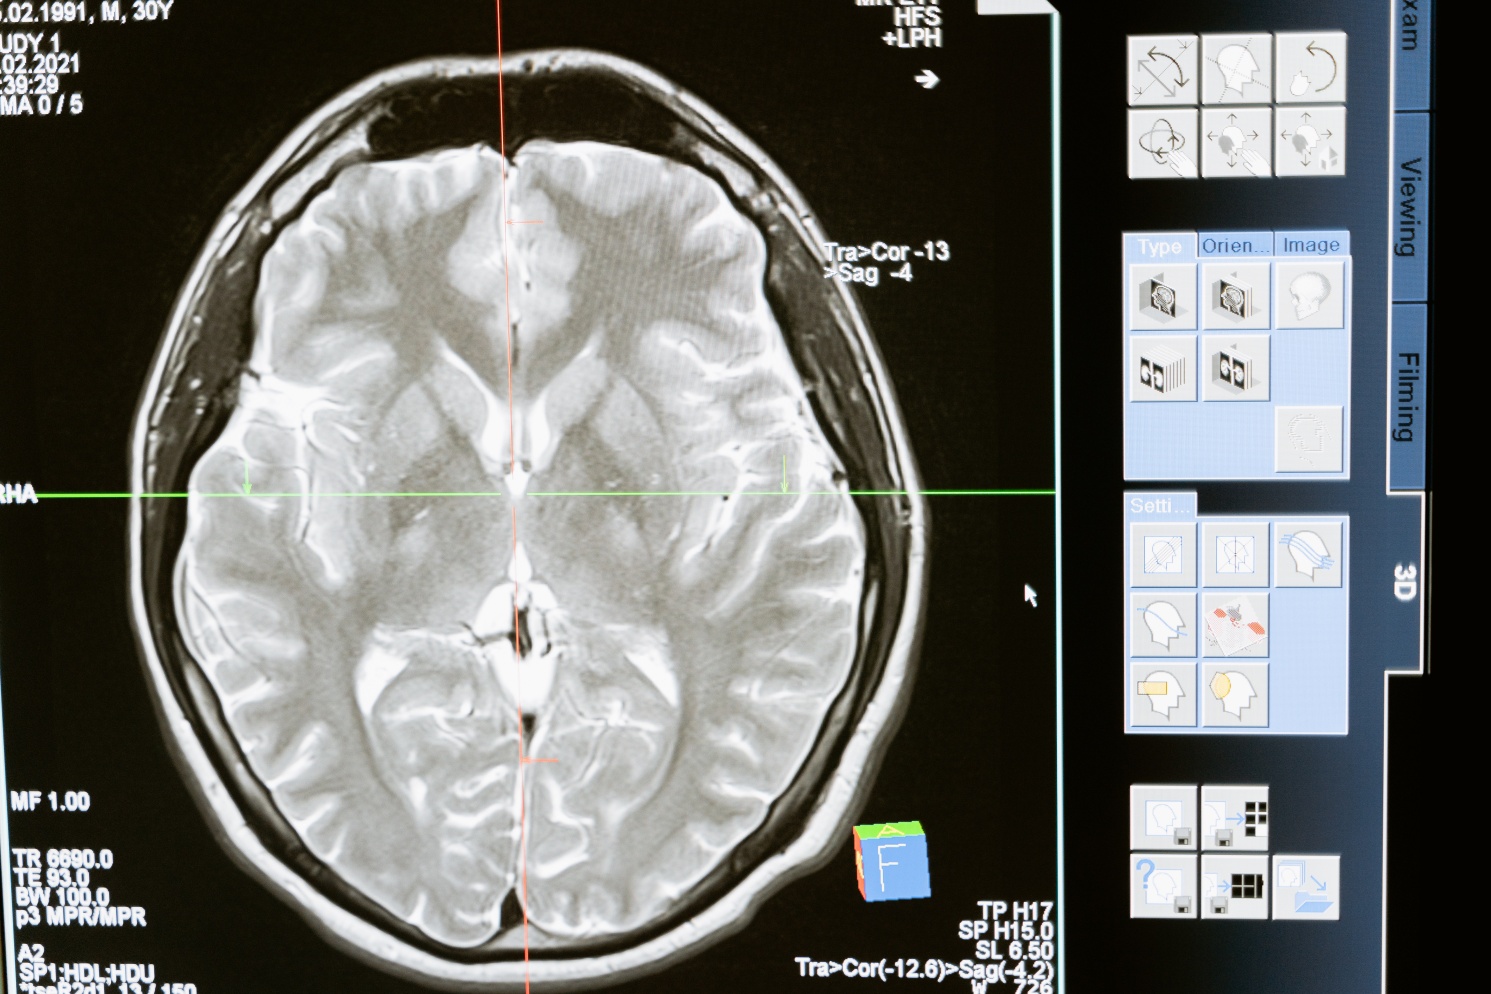

사람들은 일반적으로 뇌출혈에 비해 치료를 받을 수 있는 시간이 길다고 생각하지만 한 번 뇌혈관이 막히면 뇌세포가 죽기 시작하므로 3시간 이내에 혈전용해제를 맞거나 뇌세포 괴사를 예방하는 시술을 받는 것이 중요합니다.